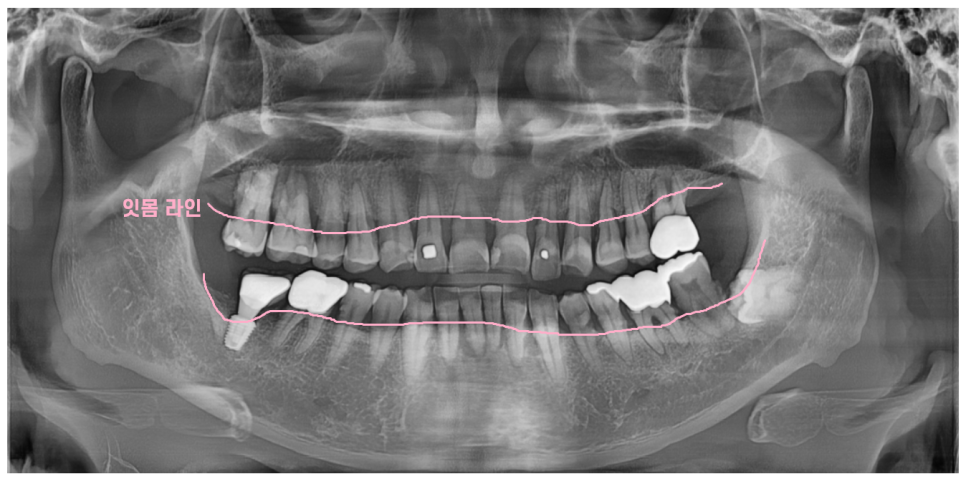

잇몸 주저앉음의 대표 증상은

치아가 길어보입니다.

잇몸이 내려가 치아 뿌리가 들어나기 때문이죠

▼사진▼

환자분은 오랜 시간 잇몸 주저앉음으로

치아 전반적으로 다 떼워진 상태입니다.

잇몸이 내려가서 치아가 흔들거렸지만

계속해서 잇몸치료 받으며 관리 받으셨는데요.